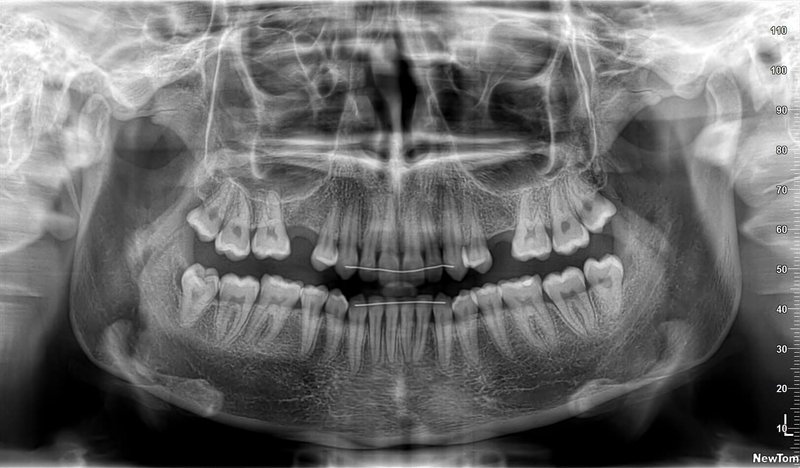

КОМПЛЕКСНЫЙ ГИБРИДНЫЙ КЛКТ ДЛЯ 2D/3D ВИЗУАЛИЗАЦИИ. ИЗОБРАЖЕНИЯ В ВЫСОКОМ РАЗРЕШЕНИИ С ЗАХВАТОМ МЕЛЬЧАЙШИХ ДЕТАЛЕЙ

GIANO HR – универсальное обновляемое устройство от NewTom для всех задач, связанных с радиографией. Благодаря полному диапазону опций 2D и 3D исследования для стоматологии оно предлагает множество особых трехмерных обследований для челюстно-лицевой хирургии, оториноларингологии и осмотра шейного отдела позвоночника. Визуализация только наивысшего качества с технологиями и опытом NewTom

NewTom GiANO HR новейшая модель была официально представлена на международном конгрессе радиологов ECR 2018 в марте в Вене. Благодаря обновленным системам механики и запатентованным механизмам работы аппарат отличается от своих сверстников Высочайшим качеством получаемых изображений, как 2D, так и 3D. Лучшее качество снимков и мы отвечаем за это! Этот аппарат заменит три аппарата! Панорамный аппарат, цефалометрическая приставка и конусно-лучевая компьютерная томография интегрированы в единую платформу. В комплекте детектор для выполнения 3D исследований с захватом области 13х16 см, Сьемный 2D CMOS детектор для выполнения панорамных исследований, и ТРГ.